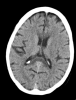

Mujer de 60 años hipertensa, dislipémica y fumadora de 2-3 cigarrillos al día desde hace 20 años que, encontrándose asintomática los días previos, sufre un síncope no presenciado precedido segundos antes de alteraciones sensitivomotoras en...

Neurología: NeurooncologíaEtiología: NeoplasiasDiagnóstico final: Metástasis leptomeníngeas por adenocarcinoma de pulmónNivel de certeza: